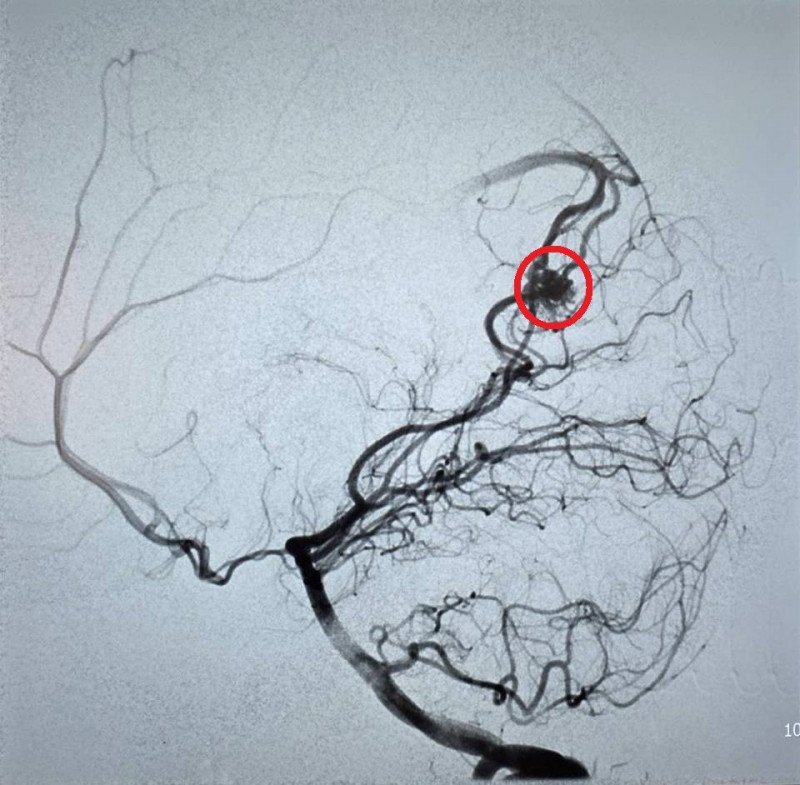

〔記者張勳騰/苗栗報導〕23歲的周小姐正值青春年華,日前卻在毫無預兆頭部劇疼痛,隨即出現嚴重的頭暈與嘔吐感,家屬見狀趕緊將她送往苗栗市大千醫院急診。經腦部電腦斷層掃描,醫師赫然發現其左側腦部有出血跡象,且出血位置極其不尋常。醫療團隊隨即展開精密檢查,證實為罕見的「顱內動靜脈畸形」引發出血。所幸進行微創血管內栓塞治療後,順利止住出血,病人症狀明顯改善,成功化解一場腦內危機。

大千醫院神經放射科醫師康靜維指出,「顱內動靜脈畸形」是一種先天性的腦血管病變。在胚胎發育過程中,若動脈與靜脈之間缺乏微血管緩衝,導致高壓的動脈血流直接衝入脆弱的靜脈,管壁便會因長期無法負荷壓力而逐漸薄弱,最終像吹太大的氣球一樣破裂,引發腦出血。這種疾病好發於30歲左右的年輕族群,臨床表現以腦出血最為常見,但也可能出現癲癇或長期慢性頭痛等症狀。

康靜維表示,顱內動靜脈畸形若未及時診斷與治療,每年約有1%至3%的出血風險。目前的治療技術已相當多元且成熟,主要包括:

1、微創血管內栓塞:透過導管進入血管,精準封堵畸形處。